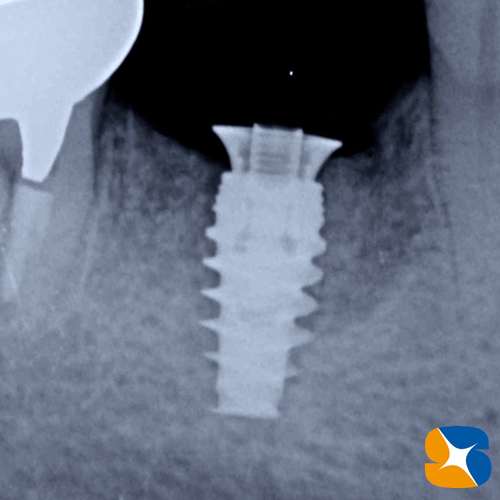

レントゲン(歯科用CT)でチェックすると、奥歯の骨が全体に溶けてなくなっていることが判明。歯を押すと沈み、離すと浮いてくる状態でしたので「やはり抜歯は避けれません。抜いたあとの所は、インプラント施術を行うことは可能です。先ずは骨の造成を行ない、土台を安定させてからインプラント施術を行いましょう」と先生にお伝えしました。

本日は、インプラントの移植手術の日(静脈麻酔鎮静下)です。

骨の状態も硬くて良好。インプラント施術も無事に完了いたしました。

ノーベルバイオケア社:アクティブ直径4.3㎜。高さ10㎜。および On1 ベースアバットを設置。